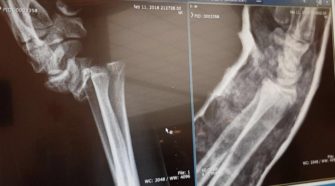

Afgelopen zondagavond kreeg een schreeuw van pijn de Jaap Eden Hal in de derde periode stil. De schreeuw was afkomstig van de 19-jarige Amsterdam Tigers forward Donny Pohlman, die even daarvoor in aanraking  met een HYC Herentals speler was gekomen. Pijn Aan de schreeuw te horen en aan de lichaamsreactie van Amsterdam’s jongste Pohlman te …